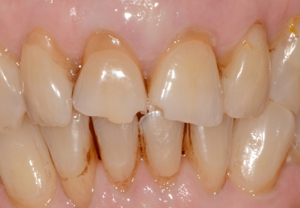

Les dents du secteur antérieur se chevauchent et 3 dents dévitalisées ont pris une teinte orangée. Le motif de la consultation est esthétique.

Les 4 facettes sont conçues, usinées et polies en 3 heures.

Collage des facettes. Les 4 facettes et le remodelage de la 12 ont évité l’orthodontie et la mutilation des dents en vue de la réalisation de couronnes périphériques complètes.